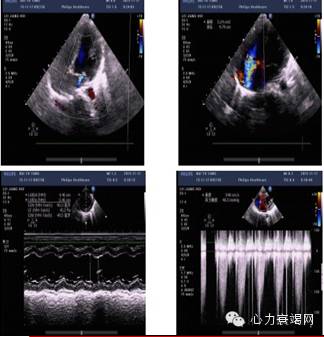

辅助检查:心动超声(11-17)

床旁超声提示:

EF值:45%

左室壁运动普遍性减低

左室整体收缩功能减低

三尖瓣中量返流

肺动脉高压(估测58mmHg)